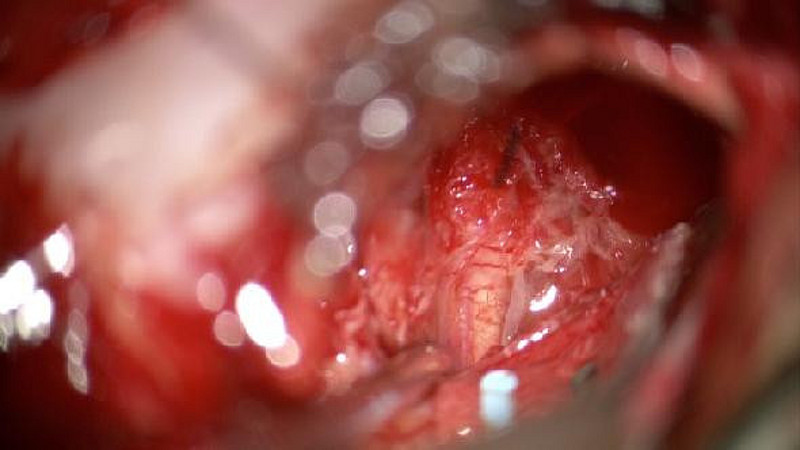

OBEN: MRT mit Akustikusneurinom, Mitte: Sicht durch das OP-Mikroskop, Unten: Billdschirm des Neuromonitoring